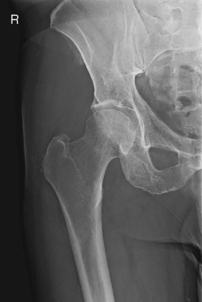

Location of the femoral head and neck regions can be accurately determined by first drawing an imaginary line between two landmarks, the ASIS and the symphysis pubis. The midpoint of this line is determined, from which a perpendicular imaginary line is drawn to locate the head and/or neck. The femoral head (A) is approximately 1.5″ (4 cm) down on this line. The midfemoral neck (B) is approximately 2.5″ (6-7 cm) down, as shown in the photo below.